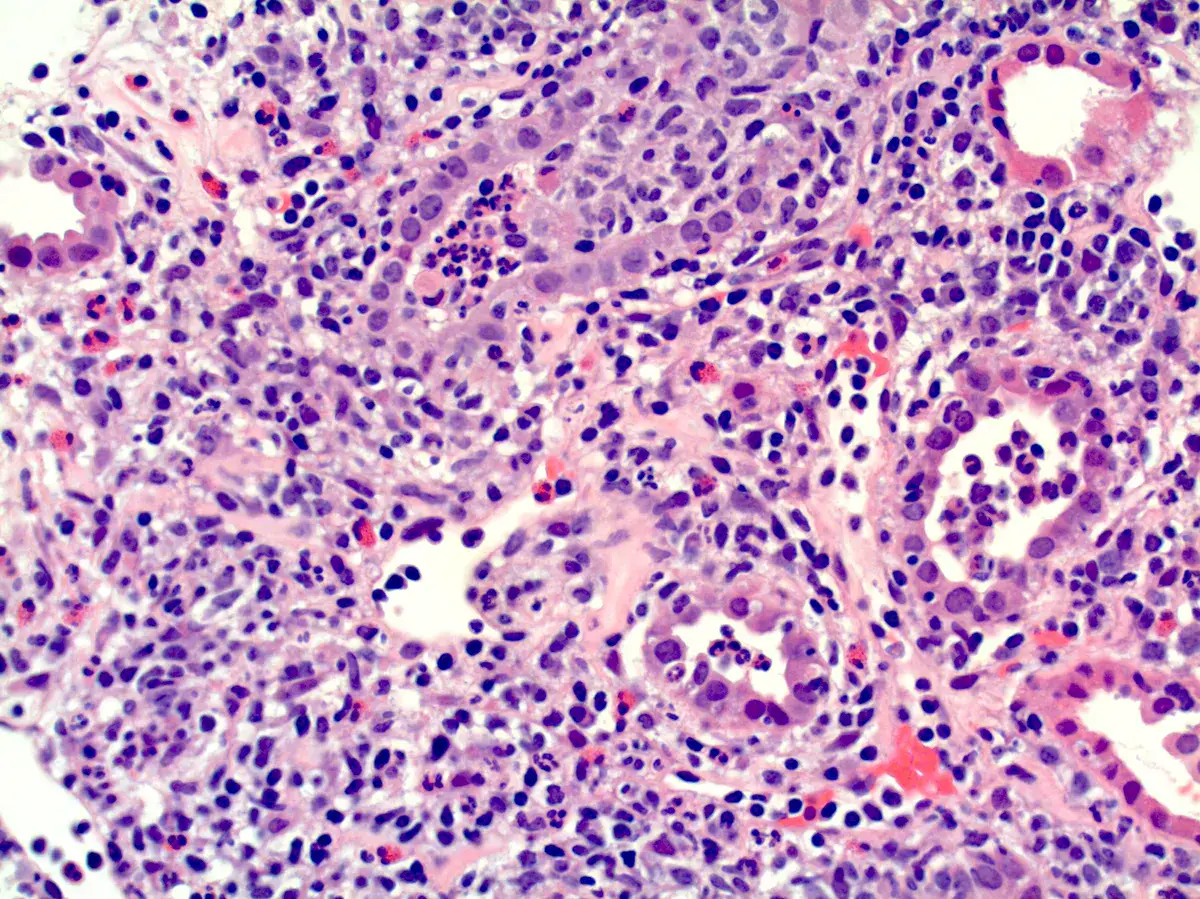

Descubra como a hipereosinofilia pode revelar rejeição mediada por anticorpos em uma paciente transplantada renal após falência do enxerto. Um caso que destaca o papel dos eosinófilos no diagnóstico diferencial e manejo clínico!

Valkercyo Feitosa